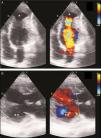

Case reportA 29-year-old woman presented with easy fatigability and chest discomfort for several months. These symptoms were insidious in onset and progressed little. There was no history of palpitations, syncope or dyspnea. She was hemodynamically stable with diffuse apex beat shifted downward and outward. The chest radiograph showed calcified LV apical and basal aneurysms. The electrocardiogram showed no pathological Q waves and normal precordial R-wave progression (Figure 1). Two-dimensional transthoracic echocardiography (iE33 xMATRIX, Philips Healthcare, Andover, MA, USA) showed moderate LV dysfunction; multiple LVAs (large apical aneurysm, moderate sized submitral aneurysm, and basal anterior aneurysm); normal contractility of the rest of the LV wall; and normal valves, other chambers and great vessels (Figure 2). The echocardiogram showed continuity of the myocardium of the aneurysms with the rest of the myocardium. Color flow Doppler showed flow in and out of the aneurysms.